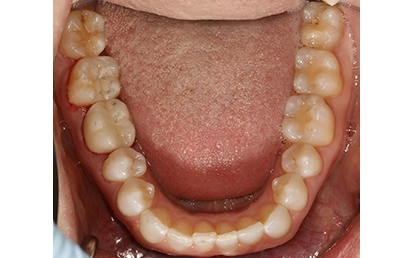

Chief Complaint: The patient presented with an upper right lateral incisor exhibiting mobility. Further examination revealed a history of endodontic treatment combined with root fracture.

Intraoral Assessment: Porcelain crowns were present on the upper right lateral and central incisors. The upper right central incisor displayed a root canal treatment, a periapical lesion, and a root fracture accompanied by discolored and inflamed gingiva. The lateral incisor had a periapical lesion deemed untreatable by the endodontist. The gingival papilla was receding between these teeth, manifesting as a visible black triangle.

Intraoral pictures of the initial condition